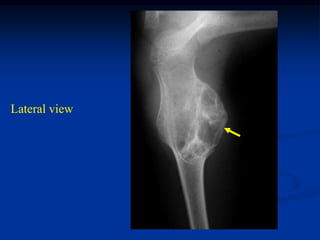

Lateral view